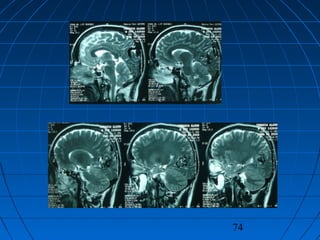

 İ.A.: 27 yaşında erkek hastaİ.A.: 27 yaşında erkek hasta

 BaşağrısıBaşağrısı

74

CERRAHİCERRAHİ

 Sol oksipital kranyotomiSol oksipital kranyotomi

 AVM’nin total rezeksiyonuAVM’nin total rezeksiyonu

 PostoperatifPostoperatif

Nörolojik Muayene ve DSA:Nörolojik Muayene ve DSA:

NormalNormal